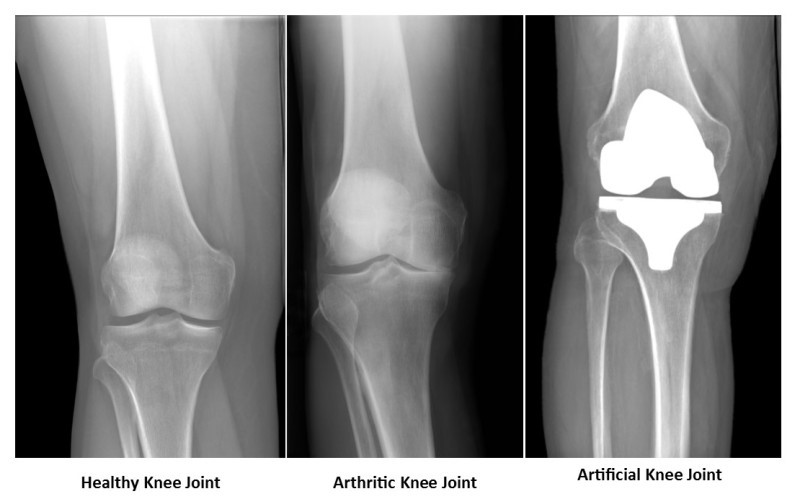

The knee is the largest joint in the body. This joint is made up of three bones. The lower part of the femur, the upper part of the tibia and the patella. The lower end of the thigh has hinged movements on the leg, and the patella can move up and down in a groove-like depression in front of the lower end of the thigh.

In the parts where these three bones are in contact with each other, their surface is covered with cartilage and this slippery surface makes these three bones move easily on each other. There is also a thick, viscous fluid inside the knee joint called the synovial fluid, or synovial fluid, which lubricates the cartilage and facilitates joint movement.

Gradual wear of the knee joint and destruction of its articular cartilage for any reason (aging, diseases and injuries caused by trauma, etc.) causes painful movement, dryness and limited mobility of the knee joint. In this situation, by changing the joint surfaces, joint movements can be improved and pain can be eliminated.

In this surgery, the damaged cartilage and bone are removed from the knee joint and replaced with an artificial joint.

How is knee replacement surgery performed:

Knee replacement surgery usually takes one to two hours. To perform this surgery, the surgeon removes the remnants of articular cartilage and a small amount of bone from these areas with incisions made in the lower surface of the femur and the upper surface of the tibia (tibia), then replaces them with metal implants. It strengthens them to the bone bed with a special substance called bone cement. He then places a strong piece of polyethylene plastic between the two metal pieces. In this way, the femurs and tibia can move together easily and painlessly.